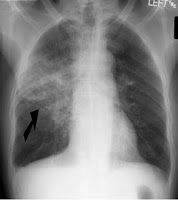

1. Rx. Focos de consolidación, con formación de abcesos y empiema